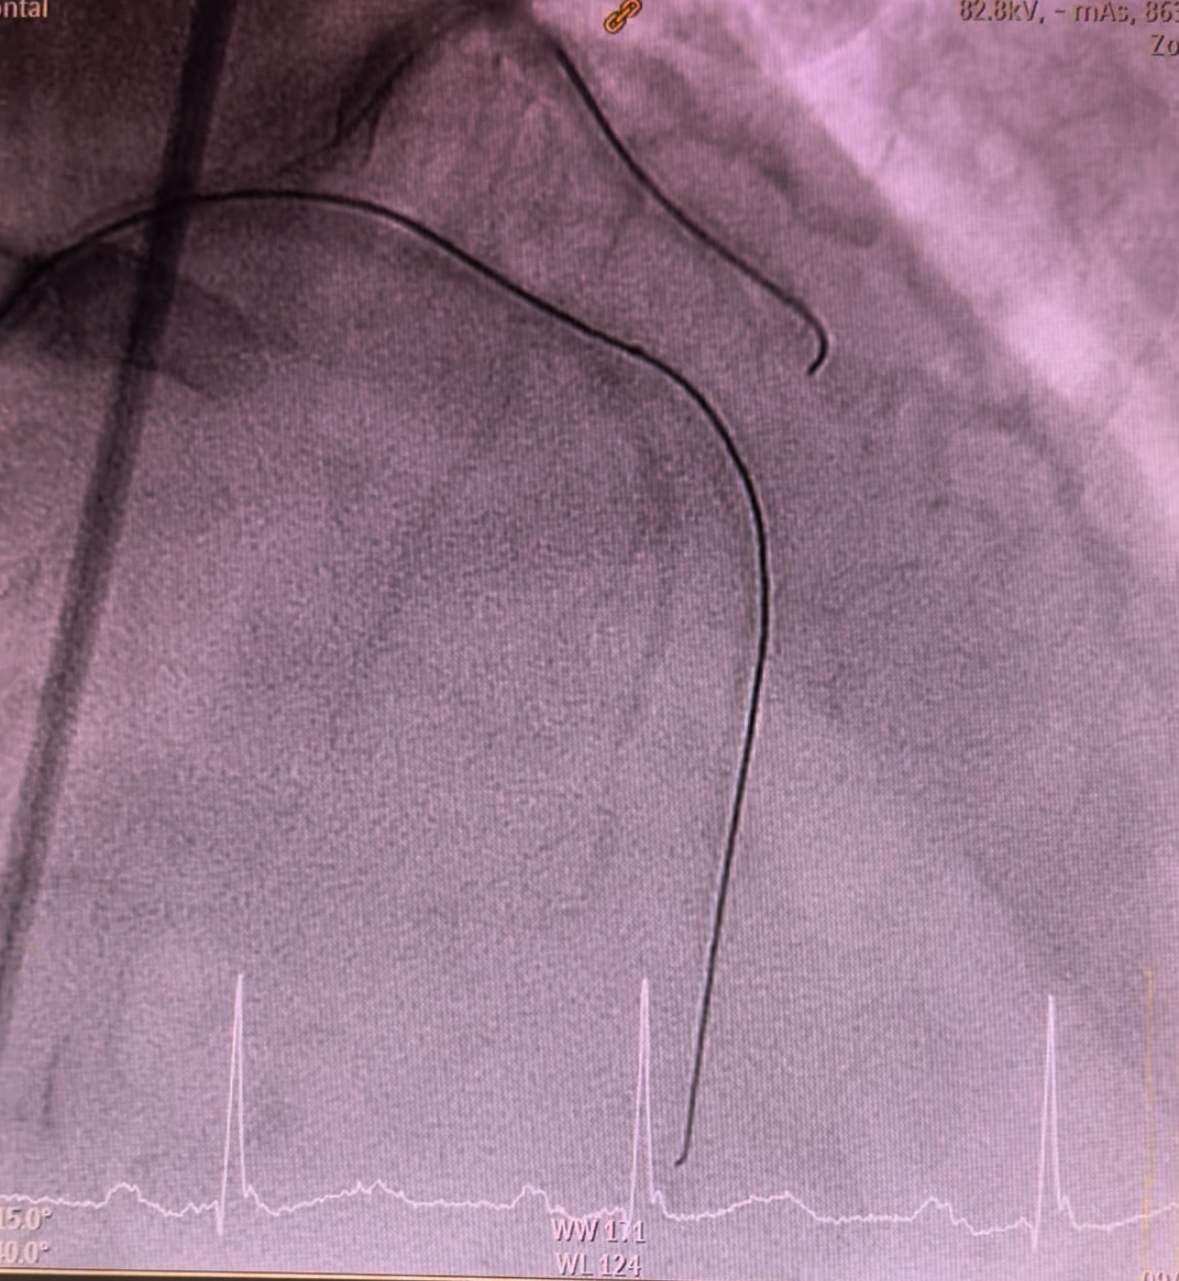

Angioplasty to left circumflex was begun by catheter engagement with XB LAD 3.5 7Fr. Wiring was done with run-through followed by lesion preparation using NC Sapphire 2.5 x 15mm inflated at 12atm. Subsequently, serial upsizing dilation was done with NC Sapphire 3.0 x 15mm inflated at 14atm. A 3.0 x 18mm stent was deployed displaying a good angiographic result. Subsequently, wiring was attempted through the LAD using Runthrough via fine cross microcatheter. Failure to pierce through the calcified stenosis has led to an escalation of guide wire to Gaia second which able to pass through successfully. Fine cross was removed using hydraulic technique with balloon inflator. Initial preparation was done by inflating NC Sapphire 1.0 x 10mm followed by 1.5 x 10mm. Thereafter, the wire was changed to Rota wire extra support via fine cross microcatheter. Rotational atherectomy was performed using 1.5mm burr, rotating at 180,000 rpm with 3 runs back and forth from proximal to mid. Further cracking was performed using intravascular lithotripsy with a 3.0mm balloon inflated at 4atm with total of 25 pulses. Further optimization was done using NC Sapphire 2.5 x 15mm and 3.0 x 15mm expanded in the mid and proximal segments respectively. Two stents sized 3.0 x 38mm and 3.5 x 38mm were respectively deployed at mid and proximal segment via guide extension. Expansion optimisation was done with a 3.5 x 15 NC Sapphire achieving TIMI 3 flow and reestablishing the flow through the side branches.